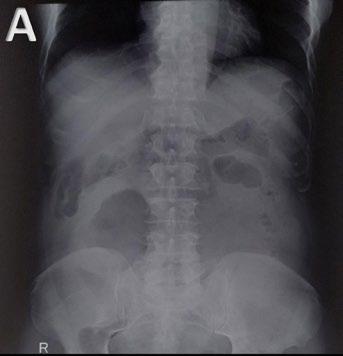

MATERIALS AND METHODS

Liver transplant candidates from 2010–2019, with waitlist placement CT scans showing nodules suspicious for HCC, according to the Liver Reporting and Data System (LI-RADS) criteria7 (LR-4/-5), and histologically confirmed after the transplant, were retrospectively included. Patients who had previously undergone locoregional procedures, exhibited tumour in vein, or had poor image quality were excluded from the analysis. HCC nodules were contoured

across arterial, venous, and delayed phases, with or without peritumoral region of 5, 10, and 15 mm. An area of ‘background’ liver parenchyma, distant from the lesions, was also segmented in each phase.

A total of 107 RFs, both directly extracted from segmentations, and normalised for the ‘background’ parenchyma, were obtained using PyRadiomics (Python Software Foundation, Beaverton, Oregon, USA). The normalisation was conducted by calculating the ratio between the RFs extracted from the VOI, and those extracted from the background segmentation. These features were then compared with each other for inter-VOIs and inter-phase relative change, while autocorrelation was assessed using Spearman’s rank correlation coefficient. RFs with relative change <10% and rank correlation coefficient >0.90 were considered non-informative. Informative RFs with different distribution in patients with and without posttransplant recurrence were selected to build multiple logistic regression models. Prediction of post-transplant recurrence was assessed by comparing the areas under the curve from receiver operating characteristic analysis and goodness-of-fit, expressed as the value range of Tjur’s, McFadden’s, and Nagelkerke’s R2 .

RESULTS

The CT scans of 53 patients were selected, resulting in a total of 1,032 segmentations from 86 nodules, with eight (15%) recurrence cases. When varying VOIs and phases, the proportion of noninformative RFs, indicating insignificant differences between the VOI and liver background, were 14–26% and 16–34%, respectively, while 4% of RFs showed autocorrelation >0.90.

The selected informative RFs allowed the building of eight predictive models with adequate performance and goodness-of-fit,

each comprising 5–12 RFs, with an area under the curve of 0.77–0.90 (p<0.02) and pseudo-R2 values of 0.13–0.46. A predominance of models derived from the arterial phase was observed, utilising the nodule with or without a 5 mm peritumoral region as the VOI, followed by the venous phase, including a 10–15 mm margin after normalisation (Figure 1).

CONCLUSION

Selection of optimal VOI and contrast phase combination is critical to maximise post-liver transplant HCC recurrence prediction using quantitative CT imaging. Specifically, segmenting the nodule, eventually including a 5 mm peritumoral region, during the arterial phase, or the nodule with a 10-15 mm margin during the venous phase after normalisation against the liver background, appeared to be the most promising strategy.●

Figure 1: Workflow and results from the radiomic analysis of hepatocellular carcinoma nodules and peritumoural regions extracted from the waitlist placement CT scans of liver transplant candidates to predict disease recurrence.